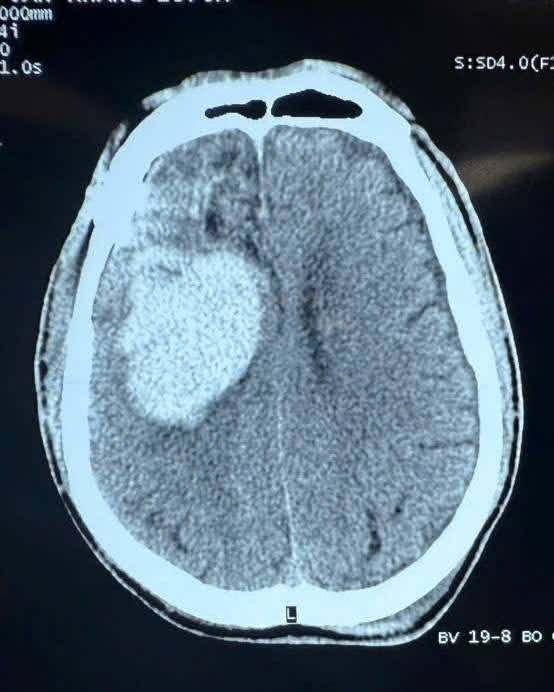

Xuất huyết nội sọ: Máu tụ dưới màng cứng (SDH); Máu tụ ngoài màng cứng (EDH); Xuất huyết dưới nhện; Dập não – phù não.

chan-tuong.jpg

Hình ảnh chấn thương não trên phim chụp - Ảnh BSCC